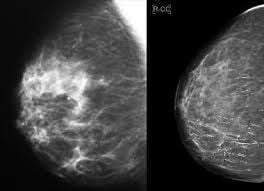

Chụp X-quang vú là phương pháp sử dụng tia X năng lượng thấp để ghi hình cấu trúc tuyến vú, giúp tìm ung thư vú. Nếu bạn được tư vấn sử dụng X-quang vú và đang chuẩn bị đi chụp X-quang vú, những kiến thức dưới đây là hết sức cần thiết.

X-quang vú được sử dụng trong sàng lọc và chẩn đoán. Sàng lọc được sử dụng ở một số lượng lớn nhiều người khi không có triệu chứng với mục đích để phát hiện được ung thư vú sớm nhất nếu có. Với mục đích chẩn đoán bệnh, khi bệnh nhân có triệu chứng phát hiện ở vú, sẽ được thăm khám và chỉ định chụp X-quang vú hoặc khi trên phim sàng lọc phát hiện bất thường, X-quang vú các tư thế bổ sung sẽ được chỉ định để nhìn thấy tổn thương rõ ràng hơn.

X-quang vú được sử dụng để phát hiện các bất thường về vú, đây không phải phương tiện để có tiêu chuẩn vàng trong chẩn đoán ung thư, tuy nhiên dựa vào phương tiện này, bác sỹ phát hiện được vị trí nghi ngờ và chỉ định các can thiệp cần thiết lấy mô bệnh phẩm để xét nghiệm nếu cần thiết. Hai triệu chứng điển hình hay thấy trên phim X-quang vú là vôi hóa và các khối.

Khối: khối là vùng xuất hiện tăng đậm độ quang trên phim X-quang vú, có hình dạng và bờ viền khác so với nhu mô vú. Kèm theo hoặc không kèm theo vi vôi hóa, bờ viền và hình dạng của khối cần được đánh giá cẩn thận dấu hiệu của ung thư. Khối thấy trên phim X-quang vú có thể là nang hoặc các khối đặc. Thông thường, phối hợp với siêu âm sẽ giúp cho bác sĩ có thêm thông tin để chẩn đoán về khối phát hiện trên X-quang vú.